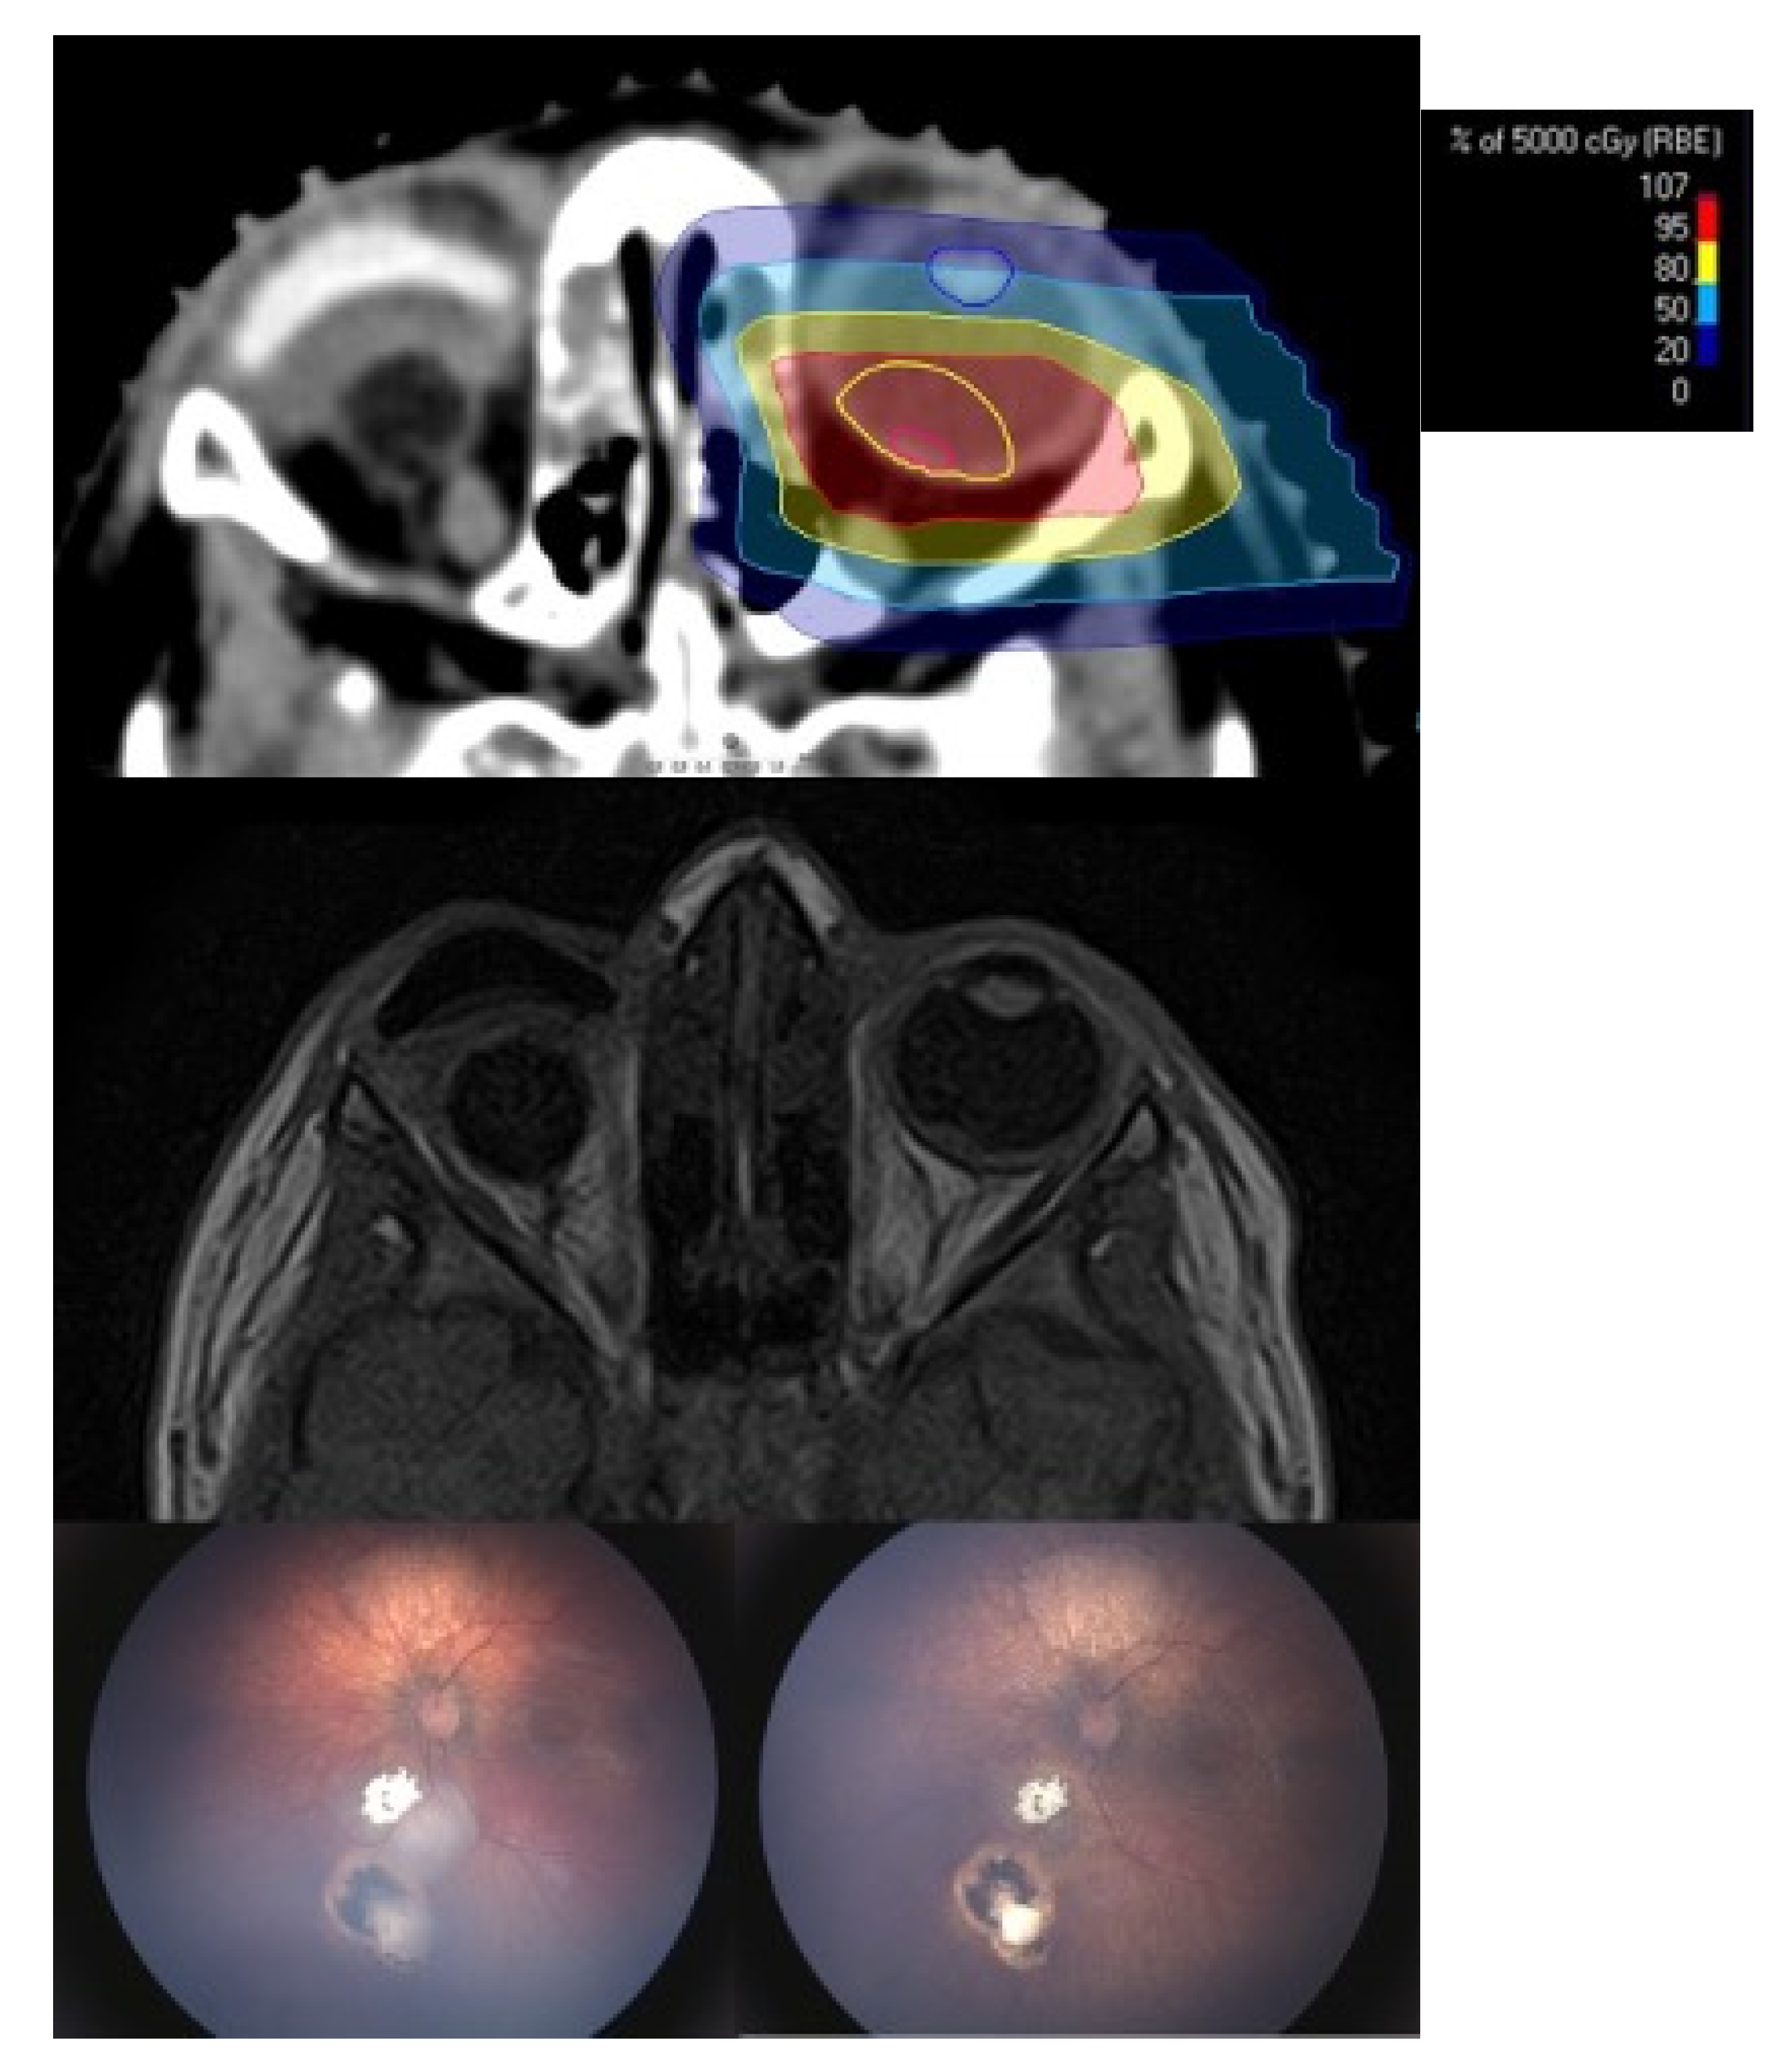

Six eyes (40%) could not be preserved after PBT and had to be enucleated after a mean time interval of 4.8 months (2–8 months). Indications for secondary enucleation were tumor recurrence at the optic nerve head with the risk of optic nerve involvement or choroidal involvement in three eyes, persisting exudative retinal detachment and intraocular bleeding with loss of tumor control and light perception in two eyes and a ciliary body insufficiency and globe hypotony after irradiation of the complete anterior segment with again loss of light perception and tumor control in another eye. Three of those six eyes were enucleated at our institution. Within the histopathological specimens viable tumor cells were found in two eyes, as it was suspected on clinical examination. Three eyes were enucleated elsewhere. In one of those eyes, no viable tumor cells were detected whereas the second case showed viable tumor cells with a massive choroidal infiltration. In the third case the course was unfavourable, since the parents refused enucleation and were treated with further intraarterial chemotherapy elsewhere in the attempt to preserve the eye. By the time the eye was finally enucleated the child had already developed systemic metastases as a result of optic nerve and choroidal infiltration and eventually died from metastatic disease. Figure 2 shows the RETCAM™ images, macroscopic images, MRI images and the histopathological slides of one patient with proven viable tumor cells after enucleation.

3.2. Radiation Induced Side Effects

Radiation induced cataract occurred in four of the nine preserved eyes, where the lens could not be spared due to tumor localization. The mean time interval between PBT and occurrence of cataract was 22.5 months (16–25 months). In three eyes, uncomplicated lensectomy was performed after a mean time of 31.7 months (30–33 months). Concerning other serious complications following PBT, one eye with involvement of the anterior segment developed a chronic ocular surface disease, which ultimately lead to a perforated corneal ulcer with the need of an emergency penetrating keratoplasty 19 months after PBT. Figure 3 shows the initial findings with a diffuse infiltrating retinoblastoma and the further clinical course with complete tumor regression and emergency keratoplasty during follow-up. So far, disease remained stable, however due to chronic surface problems VA did not improve to more than 20/200.

Figure 2. (Case 11): The first picture shows a clinical evident tumor recurrence of the centrally located type III regression 8 months after proton beam therapy. The second picture shows the corresponding MRI images with the prominent tumor and a total exudative retinal detachment. The third picture shows the macroscopic images after enucleation with a visible massive choroidal infiltration only detected by histopathological workup of the specimen.

Figure 3. (Case 7): The first picture shows the anterior segment involving tumor recurrence. This was a late recurrence with the initiation of proton therapy at 97 months of age. The tumors showed total regression. However, the child suffers from chronic ocular surface disease due to anterior segment radiation. Emergency keratoplasty had to be performed 19 months after proton beam therapy due to a perforated corneal ulcer. Even after transplantation the eye shows recurrent corneal erosions.